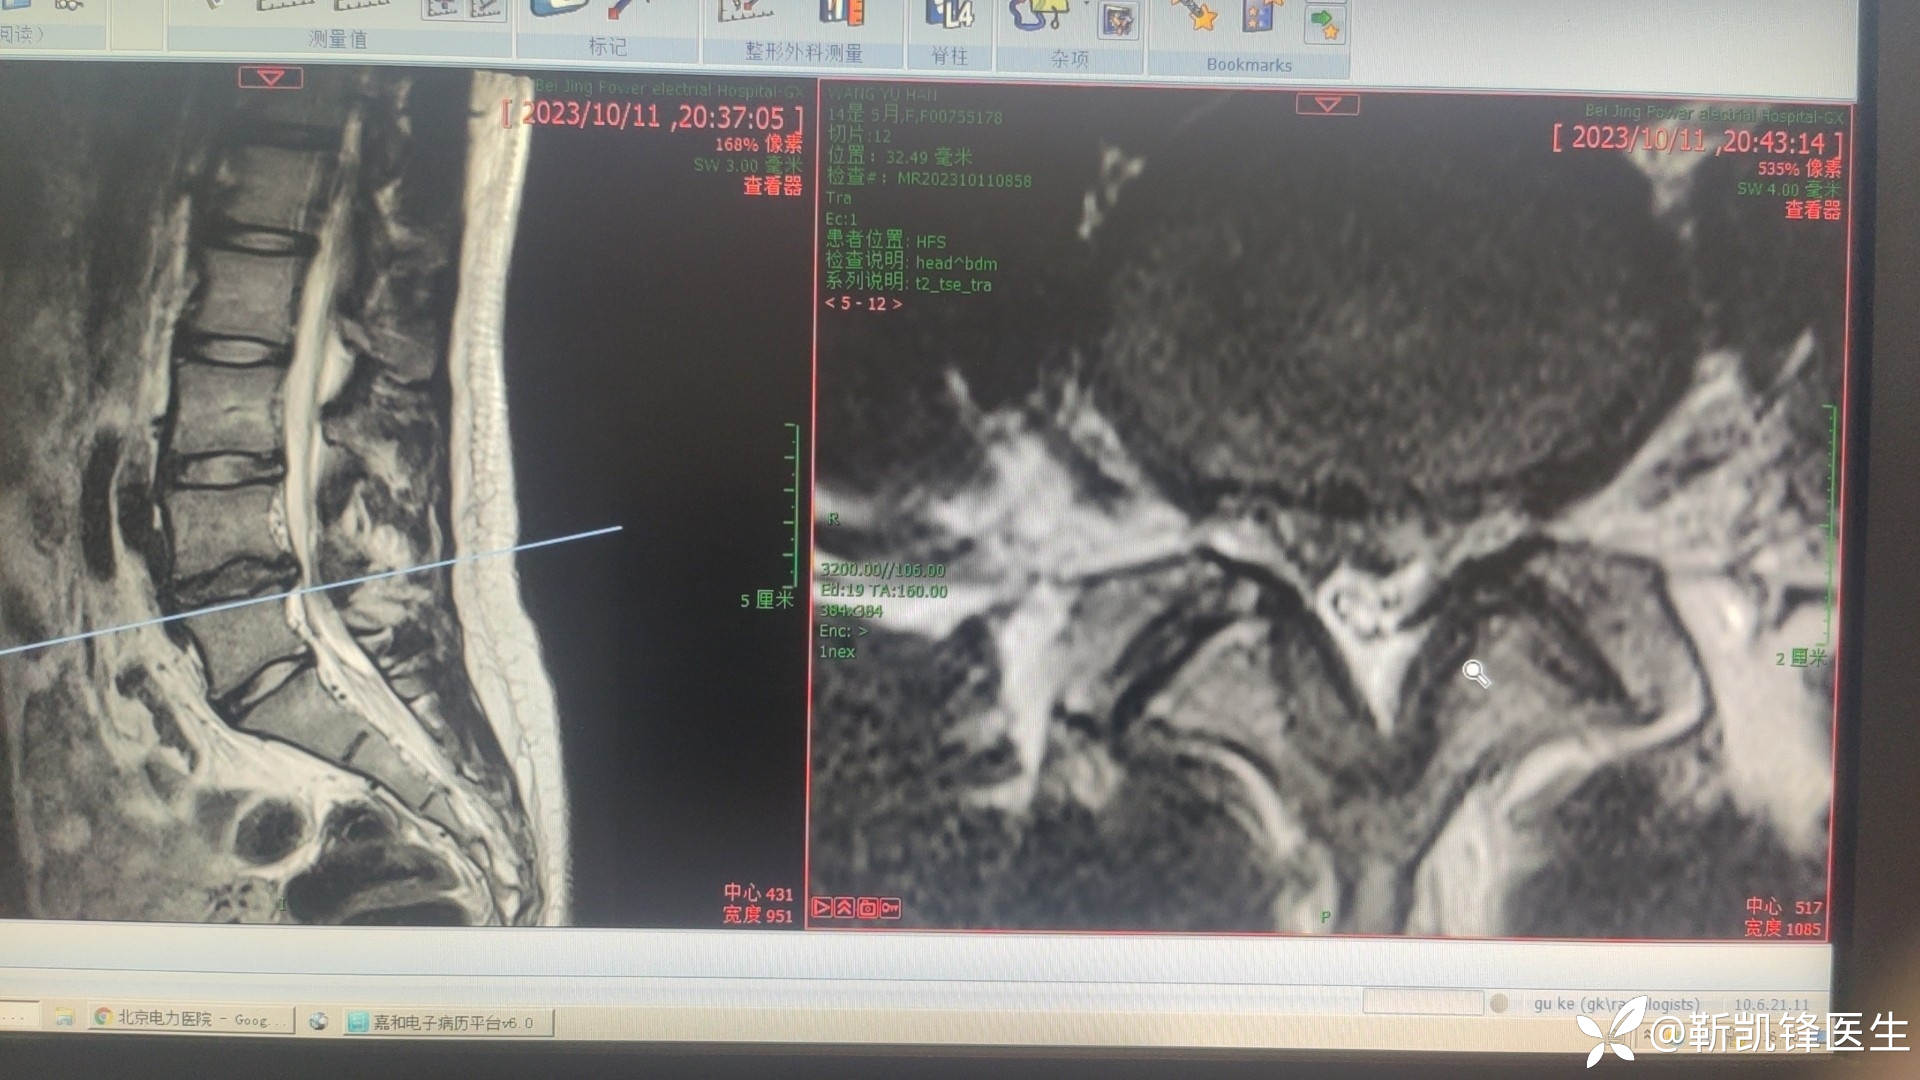

病例14岁青少年腰椎间盘突出症

门诊病人,14岁,学生,腰痛伴有双侧腿疼腿麻三个月,弯腰咳嗽导致腿痛腿麻加重,影响生活和学习。其余查体门诊未检查。请各位大佬指导,下一步治疗,继续保守治疗还是孔镜?